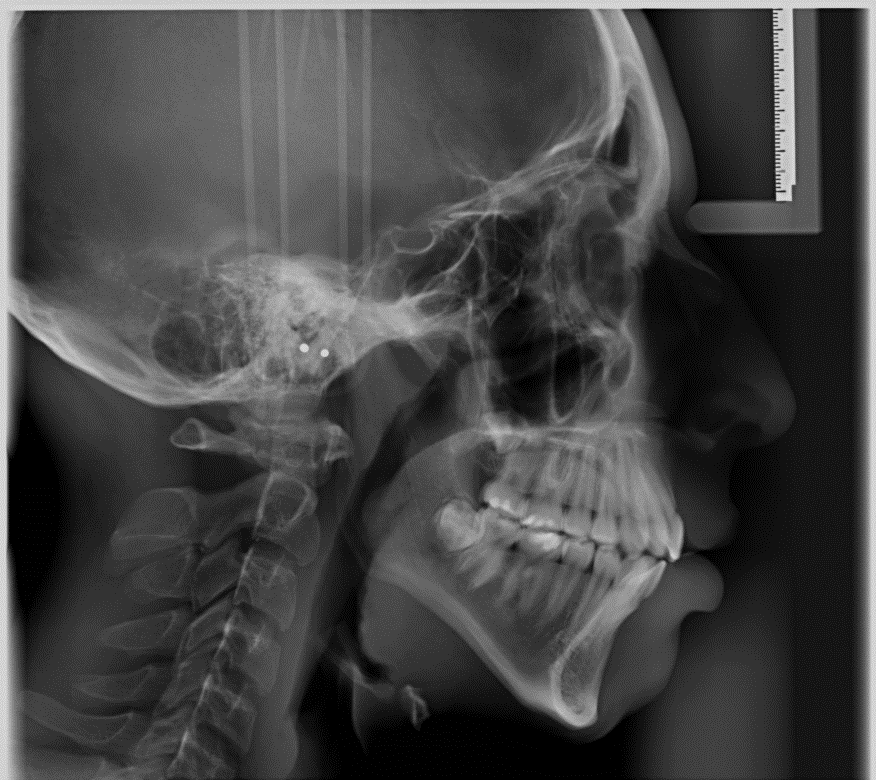

3. Teleradiografia latero-laterale (TLL), è una radiografia del craneo, eseguita in una posizione di profilo permette di valutare la posizione delle arcate dentarie rispetto alle ossa, mascella e mandibola, l'eventuale presenza di malocclusioni o morsi inversi., serve per impostare il piano di trattamento ortodontico più adeguato per ciascuno dei nostri pazienti, serve anche per valutare i diversi profili protesici nelle riabilitazioni implantari totali, quasi sempre abbinata ad una Ortopantomografia.